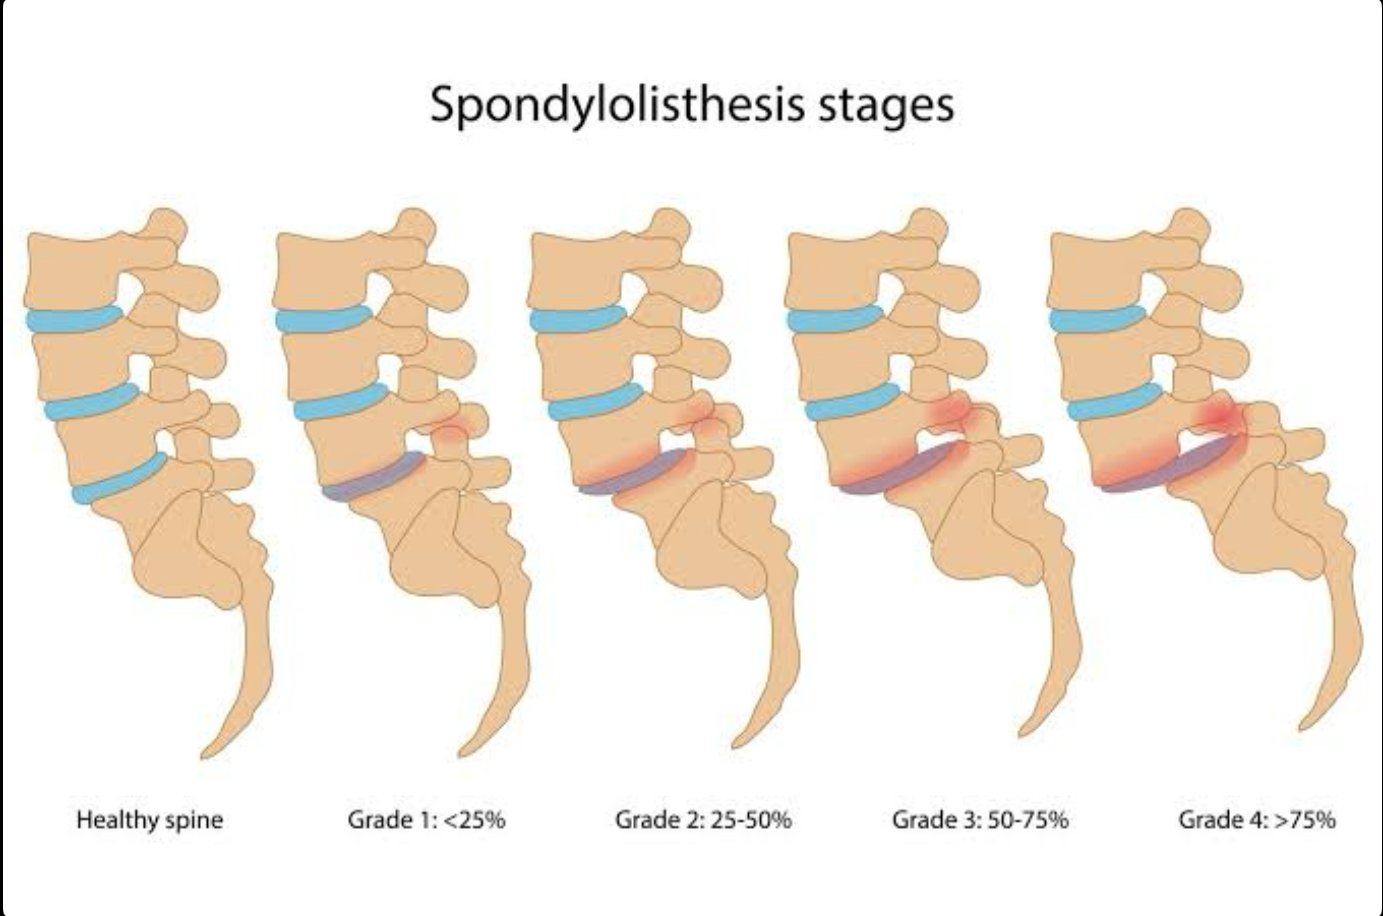

- Lumbar spondylolisthesis

MIS TLIF is recommended when spinal instability and nerve compression coexist and conservative treatments have failed.

- Stabilize unstable spinal segments

- Restore spinal alignment

| Ideal For | Complex deformity, severe instability, revision surgery | Degenerative conditions, spondylolisthesis, selected instability |